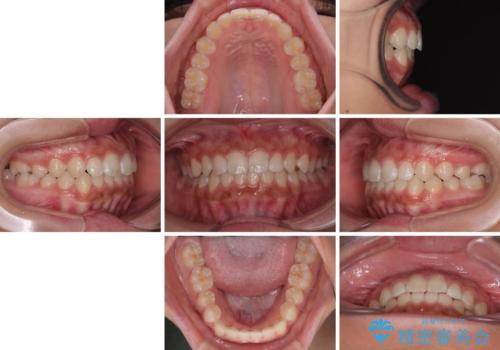

- 前歯の隙間を気にして来院された患者様です。

口元の突出感があり、小臼歯4本を抜歯して口元を引っ込める矯正治療も提案しましたが、本人は口元の突出感は気になっていないとのことで、インビザラインにて隙間やデコボコを改善することとしました。

軽度の歯列不正であったため、廉価版のインビザライン・モデレートパッケージにて治療を終えることができました。